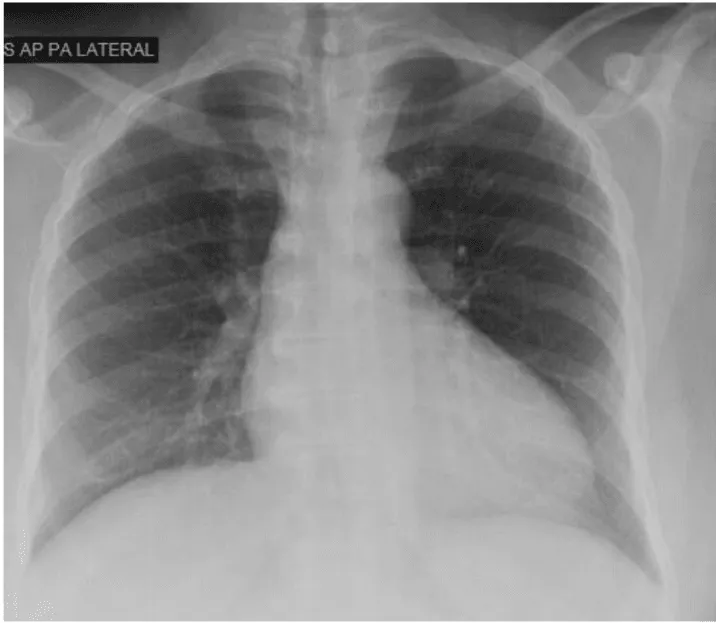

Her initial vital signs upon presentation to the hospital were; blood pressure: 161/76 mm Hg, heart rate: 96 beats per minute, respiratory rate: 27 breaths per minute. Physical exam revealed a cardiac auscultation findings of a grade 2 diastolic murmur which was loudest at the 2nd right intercostal space as well as a grade 2 systolic flow murmur. Cardiac biomarkers were elevated with initial troponin-I of 0.33 ng/mL, peak of 2.28 ng/mL and subsequent down trend. Electrocardiography (Figure 1) showed sinus rhythm with anterior and inferolateral T wave inversion and chest radiograph (Figure 2) was unremarkable. She underwent coronary angiography which revealed normal coronary arteries. The takeoff of the right coronary artery (RCA) was noted to be superior and anterior to its normal position (Figures 3A and 3B). Transthoracic and transesophageal echocardiography (TEE) revealed normal left ventricular systolic function and severe insufficiency of the aortic valve with Quadricuspid morphology (Figure 4A in Diastole, Figure 4B in Systole, Figure 4C Long Axis of the aortic valve). She underwent aortic valve replacement with a # 19mm ON-X mechanical valve. Intraoperatively it was noted that the ostium of the right coronary artery was over the aberrant leaflet. Her postoperative course was complicated by the development of supraventricular tachycardia, posteriorly localized pericardial effusion, severe hemolytic anemia, renal failure and pancreatitis leading to her death eleven days after the surgery.

Figure 2: Chest Radiograph.